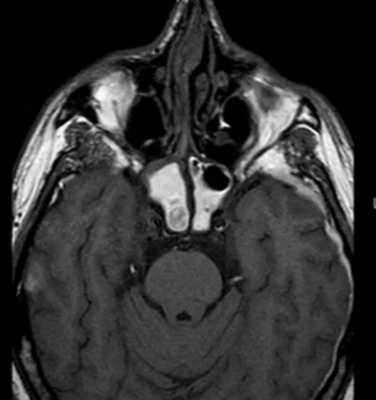

Обычно единичный очаг из плазматических клеток в костях обозначают как плазмоцитома, в то время как множественное поражение называют миеломной болезнью. Плазмоцитома практически не встречается у пациентов до 40 лет. Локализуется очаг чаще в осевом скелете. Множественные очаги при миеломной болезни также поражают кости таза, череп. Плазмоцитома возникает из костного мозга в виде безудержного размножения плазматических клеток (обычно IgG). Характерный белое Бенс-Джонса легко определяется в моче.

На рентгенограмма, КТ или МРТ поражение типично литическое, каплевидное, четко очерченное. При МРТ позвоночника такие очаги особенно отчетливо видны по замещению желтого костного мозга.